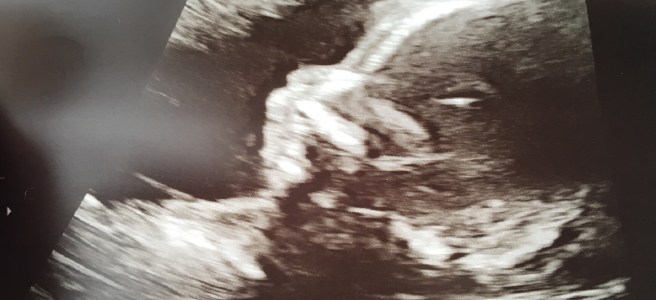

Happy New Year, everyone! We ended our year differently than we usually do, in fact it was different in so many ways. The biggest difference being that we celebrated the evening as parents with our sweet baby boy. Even though we are almost 11 months into parenthood it still feels so surreal. Usually we end … Continue reading Hello 2020